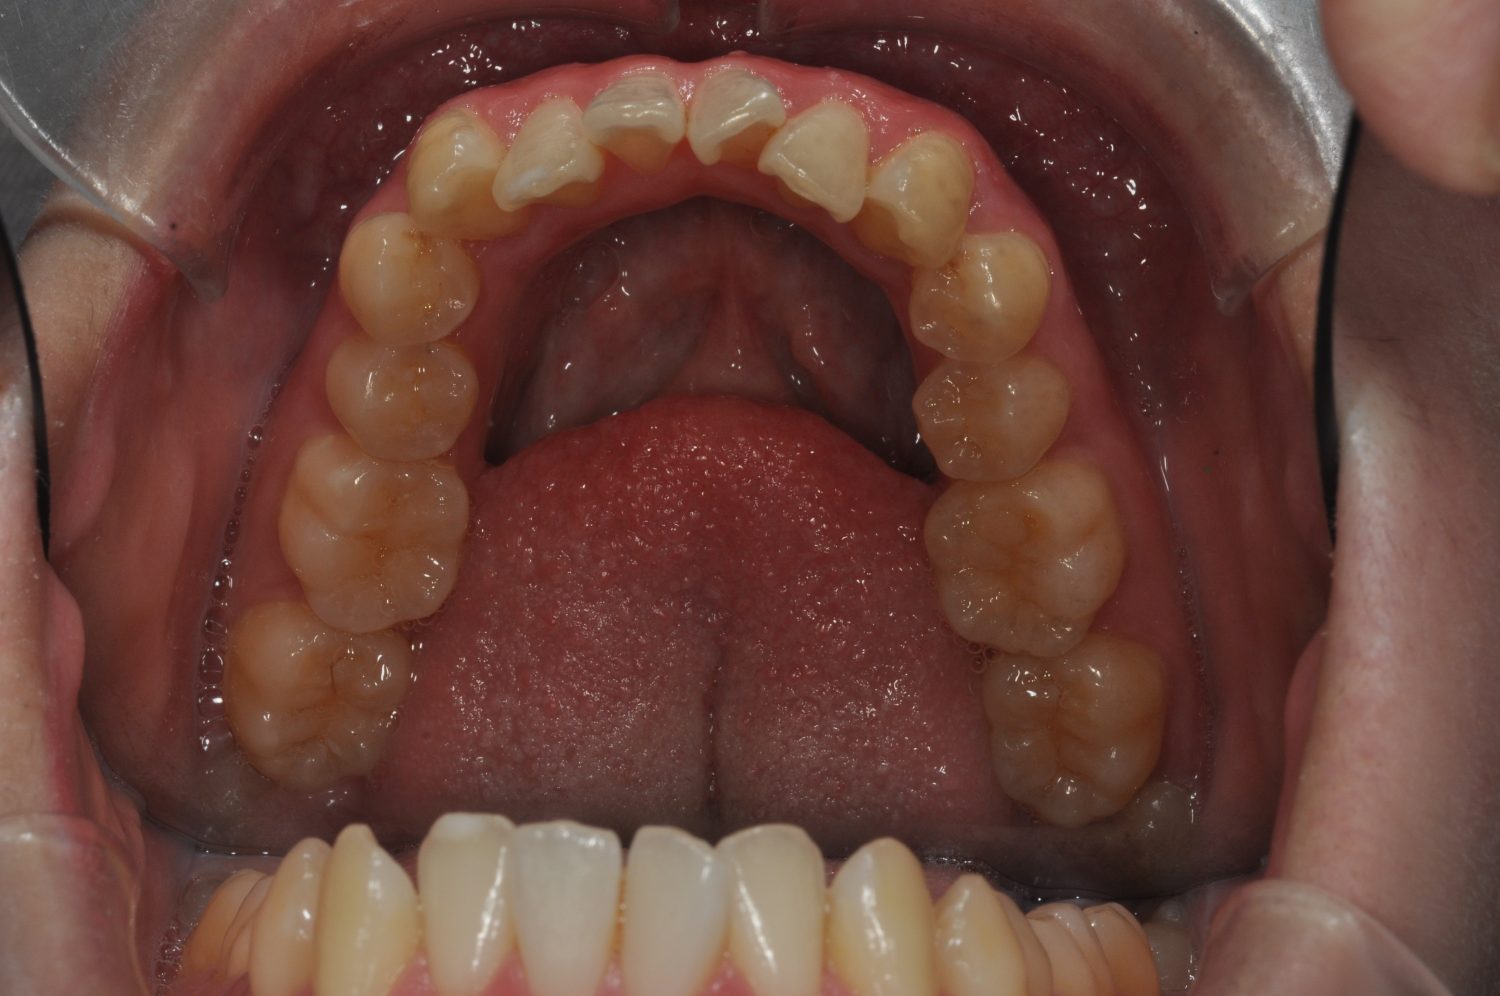

| 主訴 | 口上下顎のガチャガチャが気になる |

| 治療内容 | 歯冠幅径が大きいことから、IPRを併用した非抜歯治療 |

| 治療費 | Ⅱ期治療費:247,500円(税込) 調整料 5500円(税込)×11回 保定時:22,000円(税込) 計 330,000円(税込) |

| 治療期間 | 1年2ヶ月 |

| 治療回数 | 13回 |

| 想定されたリスク | 矯正中の清掃状況によってはむし歯や歯周病のリスクがありました。歯根吸収や歯肉退縮のリスクもありました。 |

Ⅰ期治療で前歯部反対咬合をセクショナルアーチとMPAを使用して改善した後、成長観察を行っていました。永久歯が萌出したため、Ⅱ期治療を開始することとなった。上下顎とも骨格的に問題がなかったため、非抜歯で治療を行った。